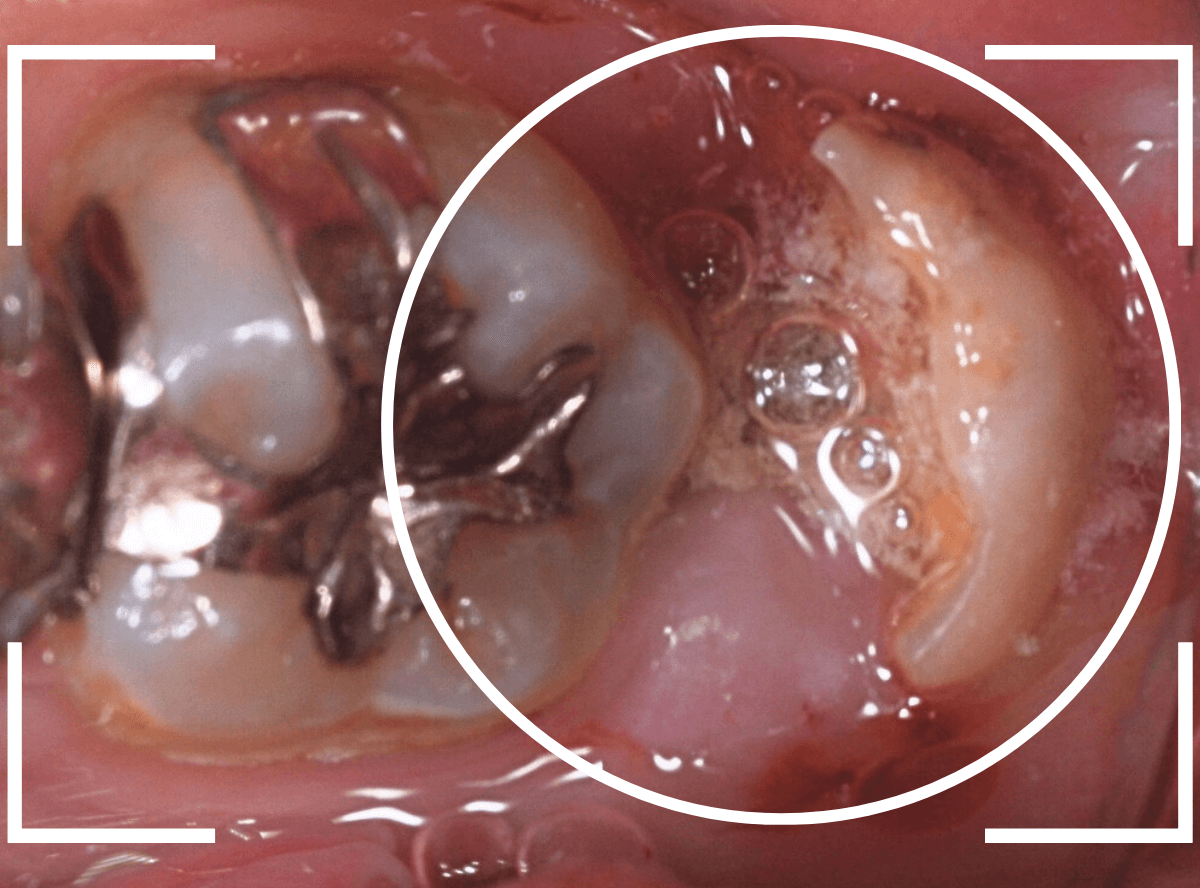

抜歯後に長期間お痛みが出たり、経過観察が必要な難しいおやしらずの抜歯ならまだしも、簡単なおやしらずの抜歯を避けてしまったがために、他の歯に悪影響を与えてしまったもったいない例も多々見てきました。

ここでは、比較的簡単なおやしらずの抜歯の例を中心にご紹介します。